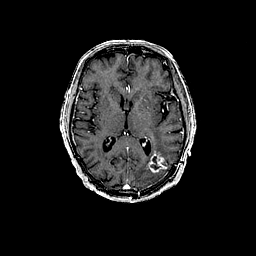

Glioma overlay -- Slice #60

[Home][Help][Clinical] Slice 60